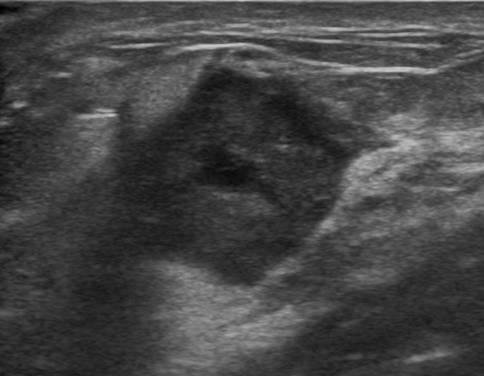

Ung thư vú

Ung thư vú - Ảnh 4

» Thông tin: Nữ giới – 54 tuổi.

» Lâm sàng: Khối tuyến vú.